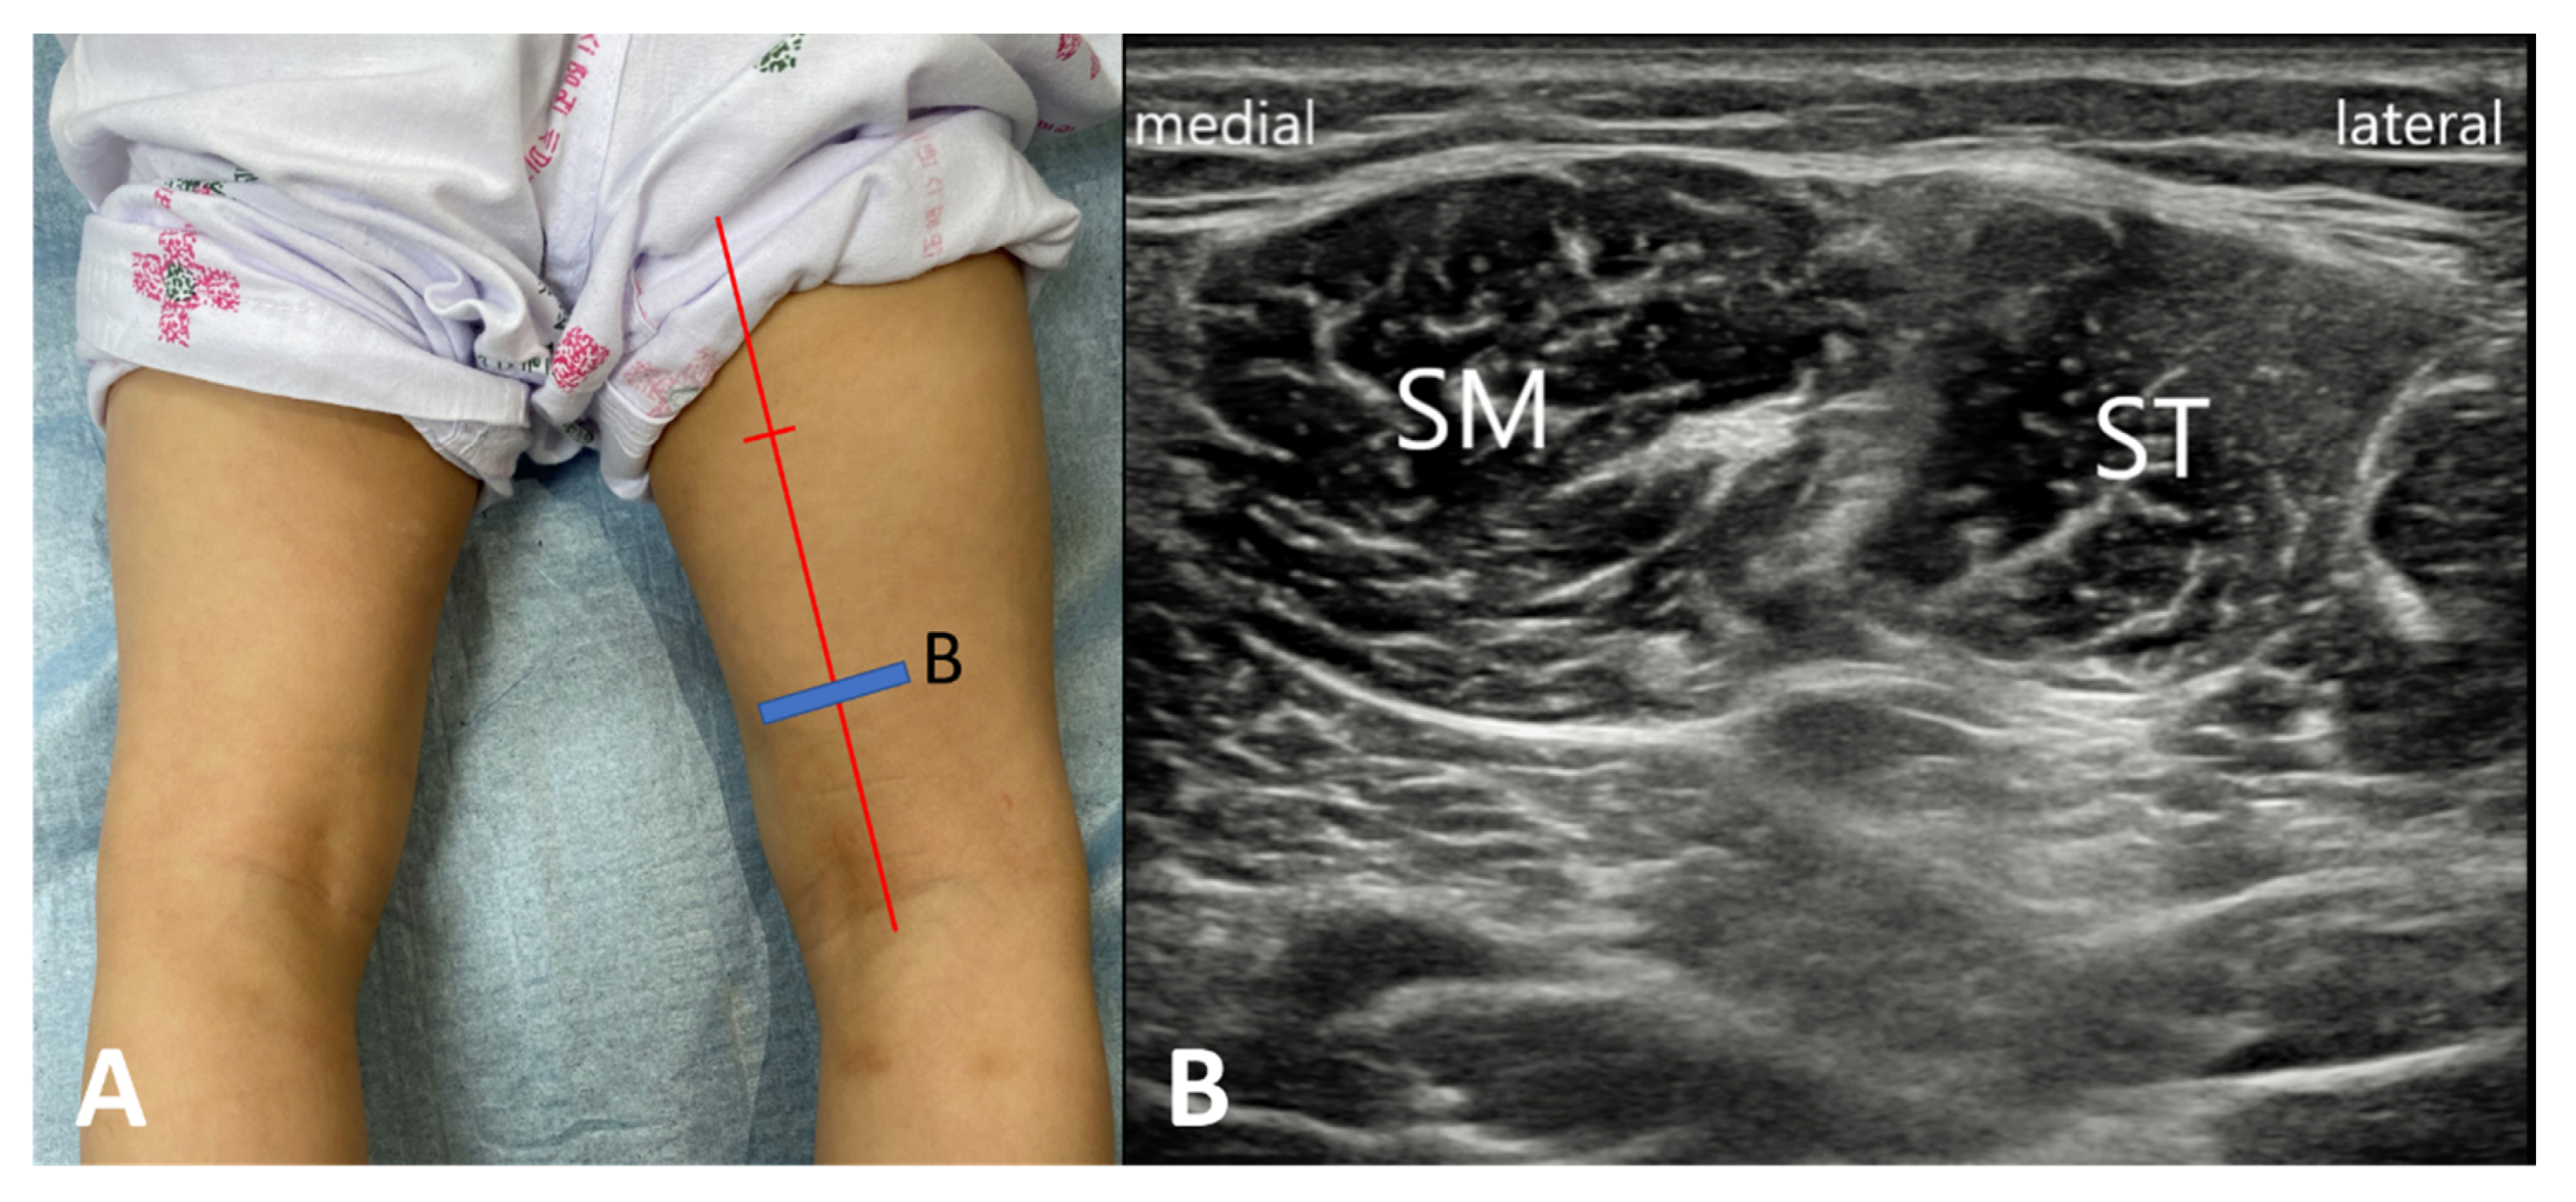

| SM | semimembranosus |

| ST | semitendinosus |